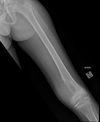

2

3

Perfectly